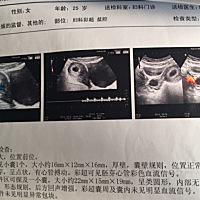

哪位姐姐指点一下,这个是怎么看的